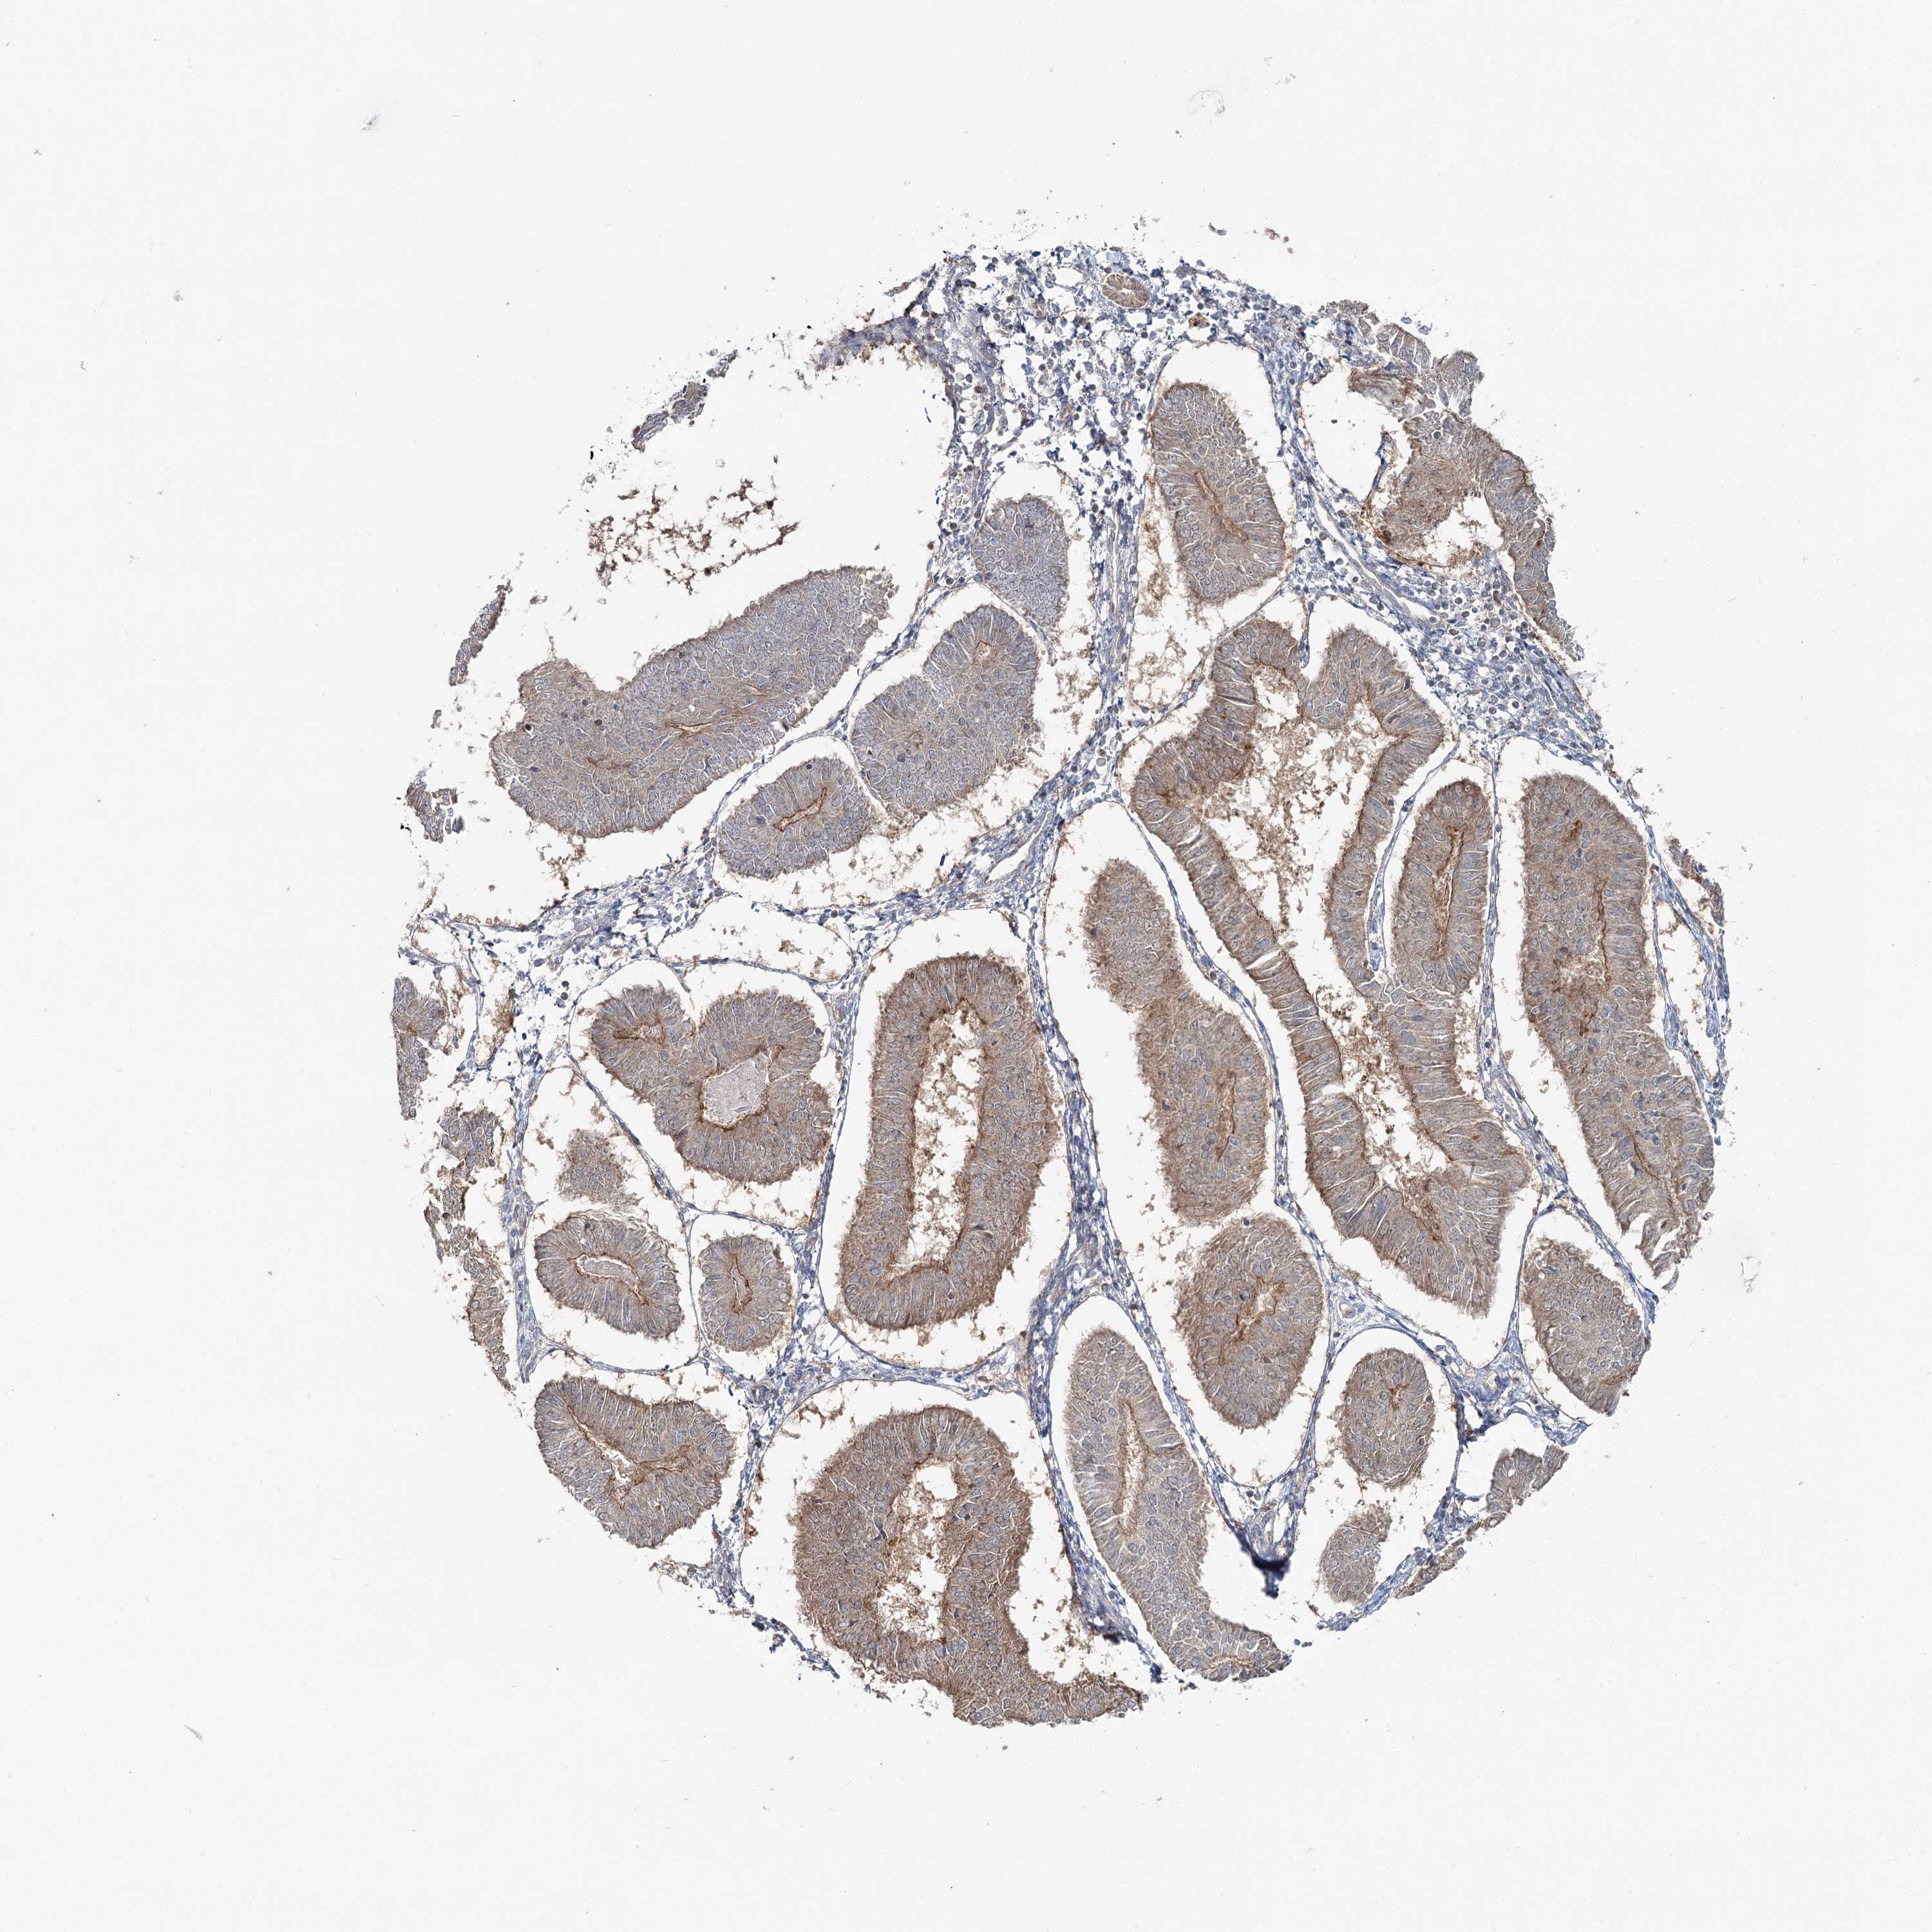

ENDOMETRIAL CANCER - Protein expressioni

A mouse-over function shows sample information and annotation data. Click on an image to view it in a full screen mode. Samples can be filtered based on level of antibody staining by selecting one or several of the following categories: high, medium, low and not detected. The assay and annotation is described here.

Note that samples used for immunohistochemistry by the Human Protein Atlas do not correspond to samples in the TCGA dataset.

Antibody stainingi

Antibody staining in the annotated cell types in the current human tissue is reported as not detected, low, medium, or high, based on conventional immunohistochemistry profiling in selected tissues. This score is based on the combination of the staining intensity and fraction of stained cells.

Each image is clickable and will lead to virtual microscopy that enables deeper exploration of all samples and also displays staining intensity scores, fraction scores and subcellular localization as well as patient and tissue information for each sample.

Antibody HPA036428

Staining

High

Medium

Low

Not detected

Intensity

Strong

Moderate

Weak

Negative

Quantity

>75%

75%-25%

<25%

None

Location

Nuclear

Cytoplasmic/membranous

Cytoplasmic/membranous,nuclear

Adenocarcinoma, NOS